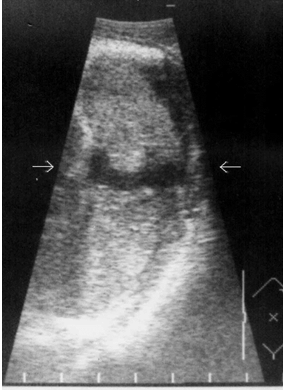

Необходимо указать, что при первичном исследовании (3–5 часов после травмы) ни в одном наблюдении не представилось возможности достоверно выявить подкапсульный разрыв селезенки в виде эхонегативной зоны. Повреждения визуализировались как нечетко очерченные участки паренхимы с незначительно сниженной эхогенностью, имевшие «смазанную» структуру, нехарактерную для паренхимы селезенки (рис 3).

Рис. 3. Эхограмма подкапсульного разрыва селезенки (3–5 часов после травмы). Зона повреждения указана стрелками.